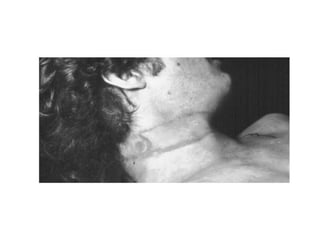

Post-mortem picture:(1) General(2) Specialfeatures    - Protrusion of the tongue.    - Dribbling of saliva.    - Hypostasis of the lowerhalf of the body.    - Neck signs:     .Elongated and the headistilted to the opposite side of suspension point.     .Ligature marks (HIGH UP in the neck, OBLIQUE, INCOMPLETE, has an IMPRINT of the ligature).  ** Homicidal, suicidal or accidental

Post-mortem picture:(1) General(2)Specialfeatures - Protrusion of the tongue. - Dribbling of saliva. - Hypostasis of the lowerhalf of the body. - Neck signs: .Elongated and the headistilted to the opposite side of suspension point. .Ligature marks (HIGH UP in the neck, OBLIQUE, INCOMPLETE, has an IMPRINT of the ligature). ** Homicidal, suicidal or accidental